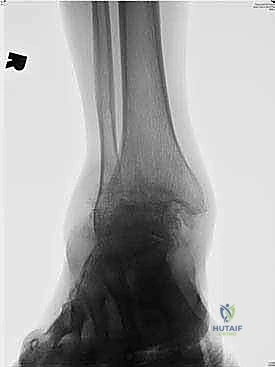

تبدأ رحلة العلاج مع الأستاذ الدكتور محمد هطيف بتقييم شامل. يتم إجراء فحوصات دموية كاملة، وتخطيط للقلب، والأهم من ذلك: التصوير الطبي المتقدم.

يعتمد الدكتور هطيف على الأشعة السينية (X-rays) والأشعة المقطعية (CT Scans) ثلاثية الأبعاد لبناء خريطة دقيقة للتشوهات العظمية وتحديد حجم ومسار المسمار النخاعي المناسب لكل مريض بدقة متناهية. يتم مناقشة كل هذه التفاصيل بشفافية تامة مع المريض.